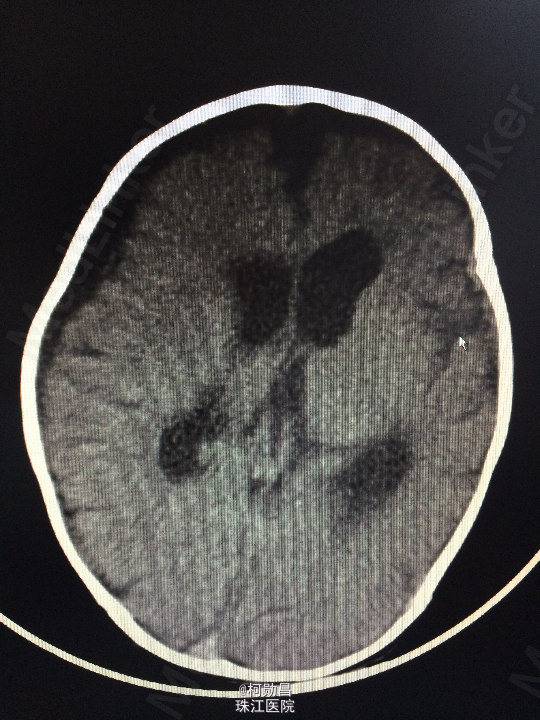

主诉:发热10天,抽搐3天 病史:患儿出生后8个月,因“发热10天,抽搐3天”入院,入院时体温39.3℃,神志不清,反应差。四肢肌张力增高,以双上肢肌力增高明显。病理征未引出。

查体:神志不清,四肢肌力增高 辅助检查:头颅CT提示脑积水并脑脊液外渗,幕上脑室扩张,右侧额颞叶硬膜下脑脊

诊断:化脓性脑膜炎伴脑积水 处理:予内科抗感染治疗,后行脑室腹腔引流术。